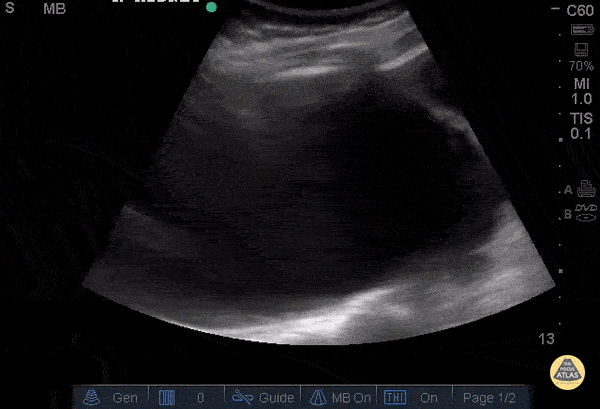

Renal/GU - Severe Hydronephrosis

An 88 year old female with history of renal stones presented with flank pain and a nonfunctioning nephrostomy tube. Bedside US showed severe hydronephrosis. This is demonstrated by dilation of renal pelvis and ballooning of renal calyces. One calyx measured approximately 15cm. It was later confirmed via CT that the nephrostomy tube had been dislodged and coiled in the abdominal muscles. Dr. Steven Greenstein, Dr. Maan Al Dubayan, Dr. Andrew Aherne - Kings County Emergency Medicine